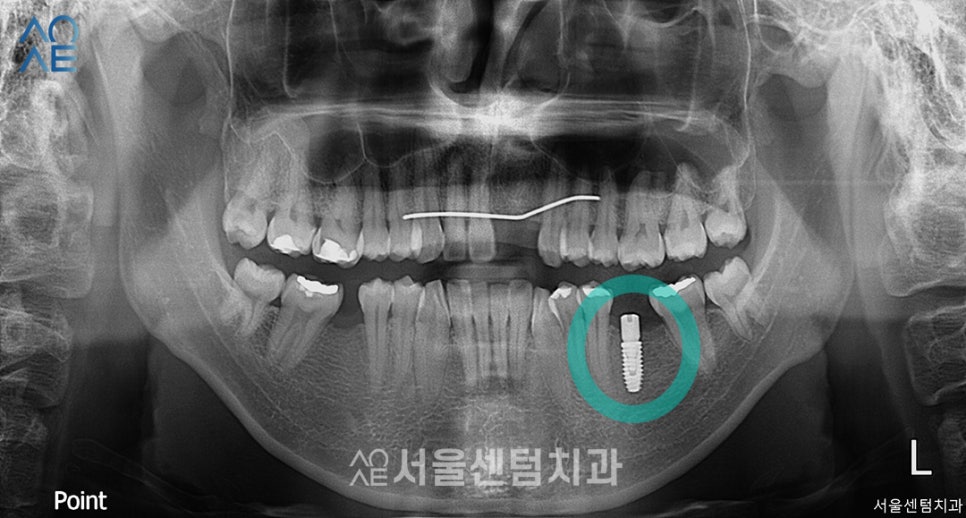

왼쪽 아래 어금니 임플란트 수술 후 모습입니다.

아직 1차만 진행한 상태이며

잇몸뼈가 부족하여 뼈이식도 함께 진행했습니다.

다음날 해피콜 진행했을 때

특별히 불편한 점이 없다고 하셔서

잇몸뼈가 잘 형성될 수 있도록

약 4개월정도 기다린 뒤

보철물을 진행하기로 했습니다.